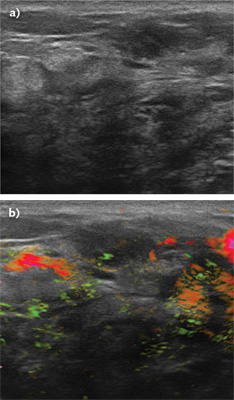

(Courtesy of Seno Medical)

Masses initially categorized as BI-RADS 4a and suspicious on ultrasound because of irregular shape and microlobulation (a) were ultimately downgraded as nonsuspicious (BI-RADS 3) with OA/US technology (b) because of benign-appearing internal and capsular vessels.

The breast-tissue imager, which combines optoacoustic technology with B-mode ultrasound, has ultrastable optomechanics to increase reliability.